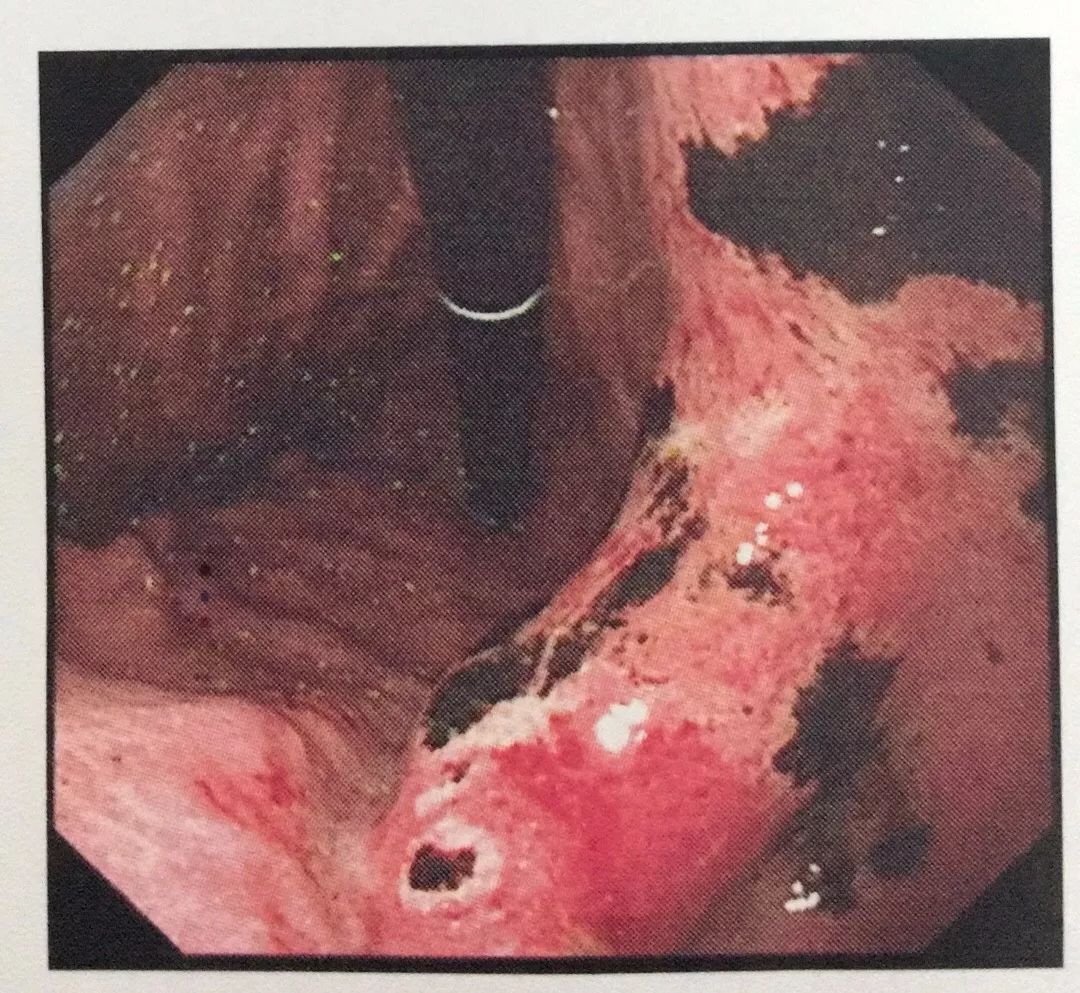

“我身体一向很好,怎么吃几根辣条就这么难受。”小张纳闷说。该院消化内科主任吴小微教授说,在无痛胃镜下,清晰显示小张整个胃部满布大片状糜烂和出血病变,还有很多溃疡形成的黑痂附着,为急性胃黏膜病变,损伤程度较重。